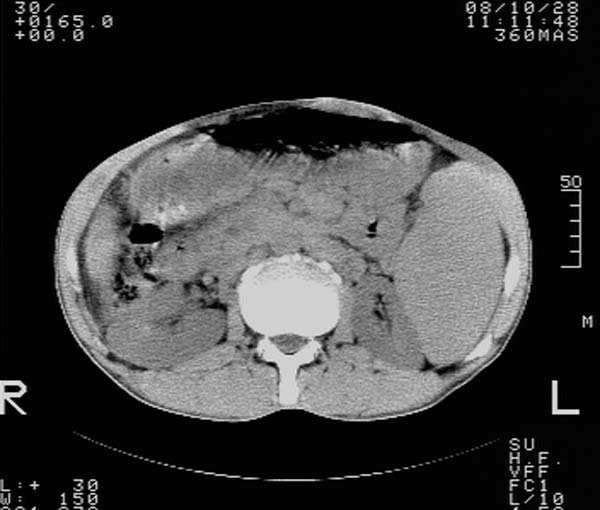

m,65y。半年前发现颈小结节,逐渐增多增大,现双侧耳后、颌下及颈部表浅淋巴肿大。胸片示双肺门增大。外院曾穿刺诊断为淋巴结核。在我科作胸腹部ct,我们觉得外院病检有误。现将图像上传请战友讨论。

纵隔内及腹膜后广泛淋巴结肿大,脾大,肝内似可见低密度影,结合病史半年前发现颈小结节,逐渐增多增大,现双侧耳后、颌下及颈部表浅淋巴肿大。考虑淋巴瘤。

我们也是首先考虑淋巴瘤。只是外院病检报告是结核。让人迷惑。肝左叶多发低密度占位,没增强不好定论。

纵隔,双肺门腹膜后多发淋巴结重大,非融合,肝脾轻度肿大,双肺野弥漫性小结节;考虑淋巴瘤,结节病可能性

纵隔内,双肺门、腋窝及腹膜后多发肿大淋巴结影,肺内小结节影,肝脾体积增大,支持淋巴瘤。肝内多发低密度影,考虑小囊肿。

考虑淋巴瘤肺、肝内转移,脾脏肿大。

纵隔内,双肺门、腹膜后多发肿大淋巴结影及颈部淋巴结肿大,肝脾体积大.结合临床,淋巴瘤可能性大。